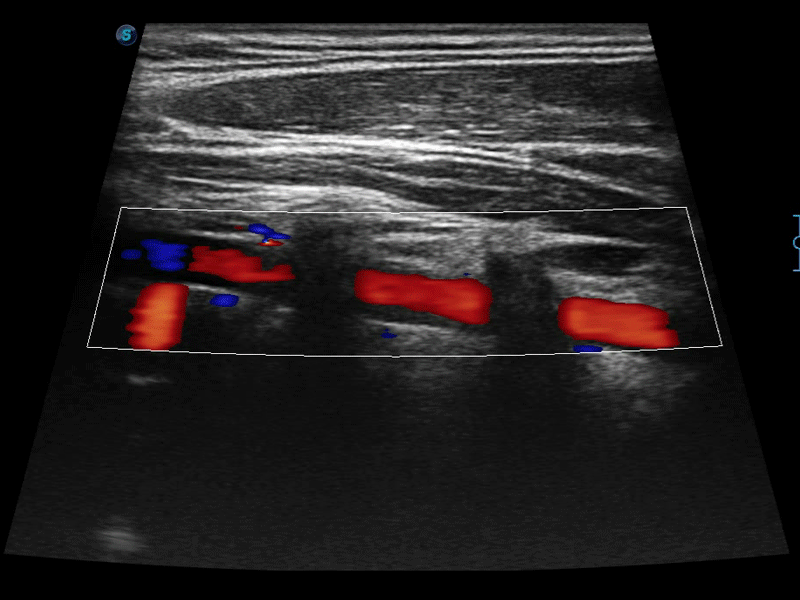

高分辨率血流成像技術(shù)提高了對(duì)低速血流信號(hào)的檢測(cè)能力。在提高空間分辨率的同時(shí),也克服了血流外溢現(xiàn)象,為用戶提供更加真實(shí)的血流動(dòng)力學(xué)信息。

通過(guò)色彩血流和實(shí)時(shí)寬景相結(jié)合,可觀察到完整的靜脈或動(dòng)脈的血流,方便醫(yī)生檢查。實(shí)時(shí)掃查過(guò)程中,如有任何操作失誤也可以很容易地進(jìn)行回掃擦除,而不會(huì)中斷掃查。